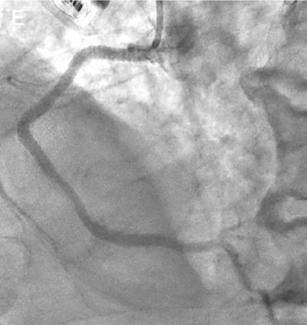

An 80-year-old man with a history of acute inferior myocardial infarction was admitted to our hospital. He had undergone bare-metal stent (3.5/28 mm) implantation in the mid-right coronary artery 22 years prior.